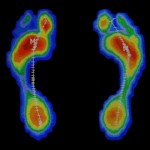

- Estudio de la pisada

- Plantillas para el deporte